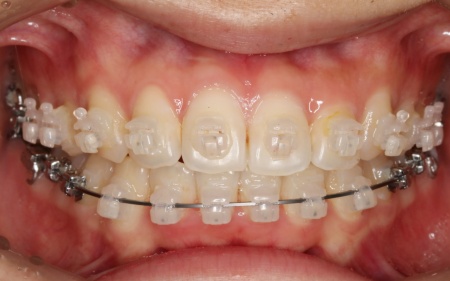

歯の表面にブラケットと呼ばれるボタン状の装置を接着し、そこにワイヤーを通して歯を移動させる方法です。

患者様は目立たない治療方法を望まれていたため、ブラケットには白く目立ちにくい「セラミックブラケット」を選択しました。

まずは歯の表面にセラミックブラケットを装着し、ワイヤー矯正で歯を全体的に移動させます。